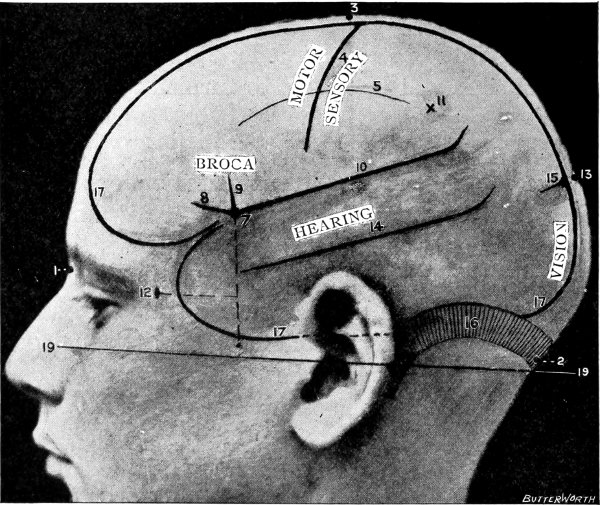

Fig. 3. The Cortical Motor and Sensory Areas.

The researches of Sherrington and Grünbaum,[2] Campbell,[3] and others tend to show that the cortical motor areas are situated entirely anterior to the central fissure or fissure of Rolando, extending above well over on to the mesial aspect of the brain, though not so far as the calloso-marginal fissure, and in the downward direction to within a short distance of the fissure of Sylvius. In the posterior direction the motor area includes the anterior boundary and part of the bottom of the fissure of Rolando, whilst in front it spreads, by means of gyri annectantes, on to that part of the brain which lies anterior to the precentral sulcus. The anterior termination is indefinite, but the motor strip is, on an average, not more than 3⁄4 inch in breadth.

This motor strip corresponds, from above downwards, to the movements of the contralateral lower extremity (toe to hip), trunk, upper extremity (shoulder to fingers), neck and face. It is a point of some general utility to bear in mind that the temporal crest intervenes approximately between the regions responsible for the movements of the upper extremity (above the crest) and those for the movements of the head and face (below the crest).

On the left side of the head—in normal right-handed individuals—the motor speech area of Broca corresponds to the third left frontal convolution, in the angle between the anterior and posterior horizontal limbs of the Sylvian fissure.

The ‘primary registration’ of ‘common sensation’ occurs in the post-central gyrus, immediately posterior to the fissure of Rolando. This tactile area occupies a position behind the fissure of Rolando[9] similar in extent to that occupied by the motor area in front. It commences at the bottom of the fissure of Rolando and extends backwards over rather more than half the exposed area of the post-central convolution. It reaches down to near the Sylvian fissure and extends over on to the mesial aspect of the brain. Furthermore, it is probable that sensation in any given part lies on more or less the same level as the corresponding motor area.

Immediately posterior to the tactile area and occupying the posterior and upper part of the post-central convolution, the area responsible for muscle-sense is situated.

Stereognosis—memory pictures, object perception, &c.—is referred to the superior parietal lobe.

Primary visual impressions are received in the occipital lobe, more especially on the mesial aspect thereof.

Finally, the four areas concerned in speech—motor speech, writing, reading, and hearing—are anatomically separated from one another and yet closely associated, so much so that one can hardly be involved without the other. The motor speech centre of Broca has already been mentioned as occupying—in right-handed individuals—the posterior part of the third left frontal convolution. Writing lies immediately above and in front, in the posterior part of the middle frontal gyrus, auditory impressions are received in the posterior and upper part of the first temporo-sphenoidal lobe, whilst the power of reading is dependent on the integrity of the supramarginal and angular gyri (see also Fig. 57).

Smell and Taste lie in close relation to the anterior pole of the temporo-sphenoidal lobes.